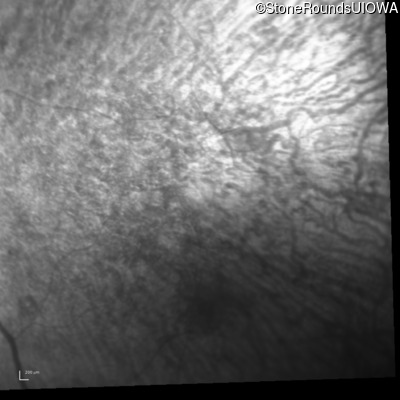

Infrared Fundus Photograph - Right - 10/200

Exemplar